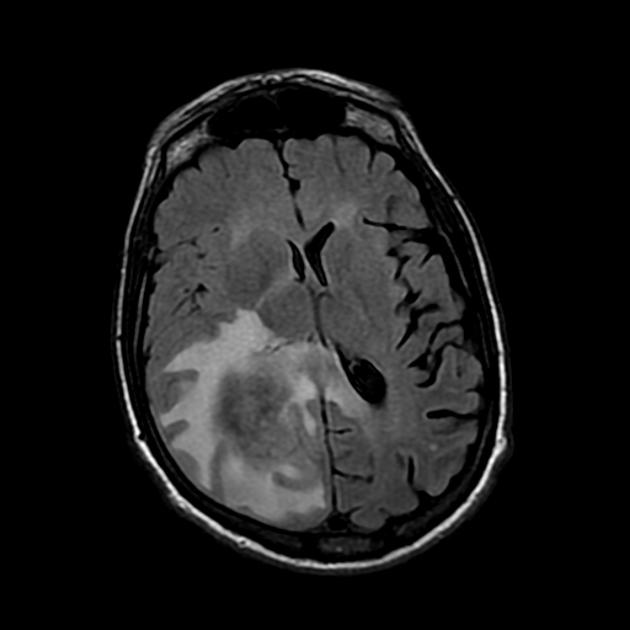

A detailed history and physical evaluation with particular attention to time course and nature of symptoms, followed by an MRI of the brain is the usual initial workup. The T1 MRI shows a hypointense or isointense lesion, and T2/FLAIR shows variable surrounding edema. T1/Gad shows homogenous enhancement without ring enhancement and lacking central necrosis. Ring enhancement occurs more often in immunocompromised patients.

MRI